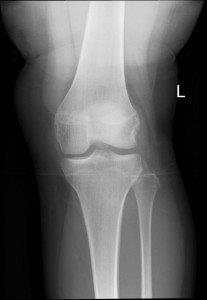

Avulsion of tibial spine (insertion of cruciate ligament)

Avulsion of fracture of lateral tibial condyle (Segond Fracture). Associated with ACL and medial meniscus injuries